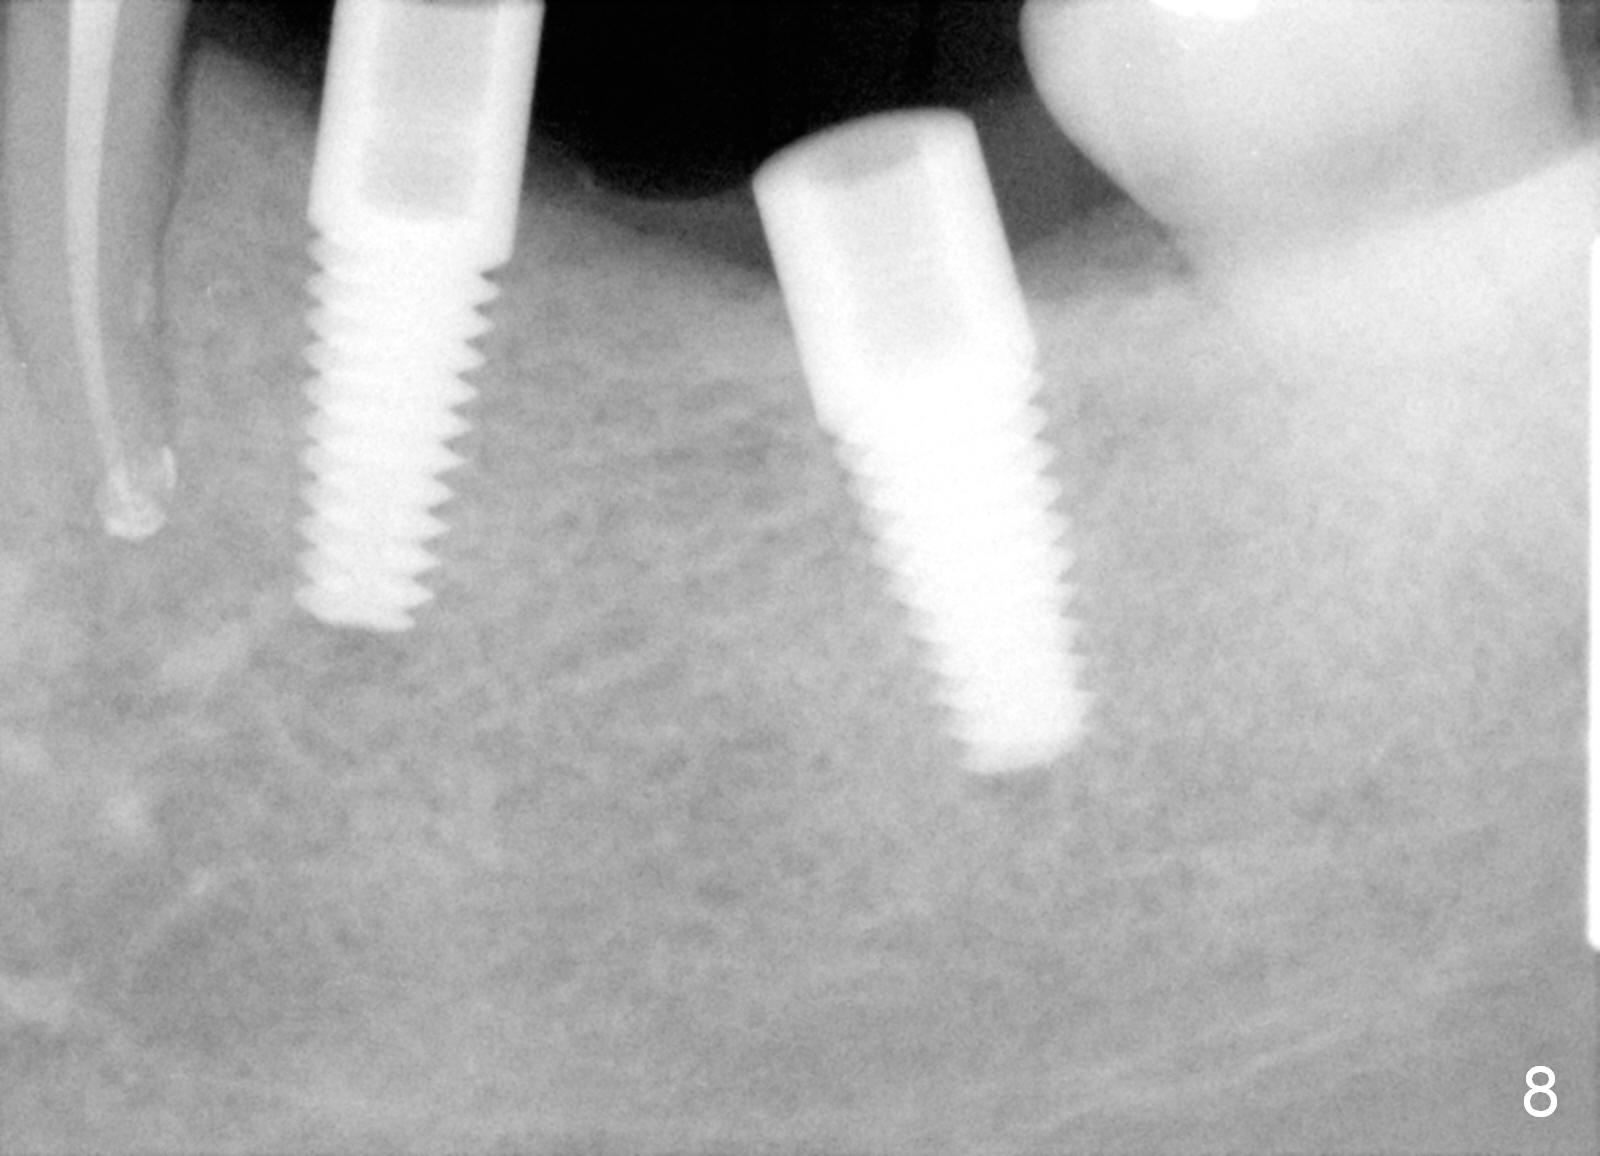

One year 2 months post root canal therapy at #20 (Fig.4), osteotomies are initiated at #18 and 19.  The trajectory at #19 is subsequently corrected (Fig.5); that of #18 should be also corrected (arrow).  The fact of the narrow ridge (Fig.6) is also ignored intraop.  Without further adjustment, the osteotomies are enlarged (Fig.7) and the implants are placed (Fig.8: 4.5x14, 5x14 mm).  As expected, the buccal coronal implant surface is exposed.  The buccal plate is decorticated with placement of autogenous bone graft.  Periodontal dressing is applied.  Postop, the wound is infected with wound gapping.  With irrigation, the wound finally heals.